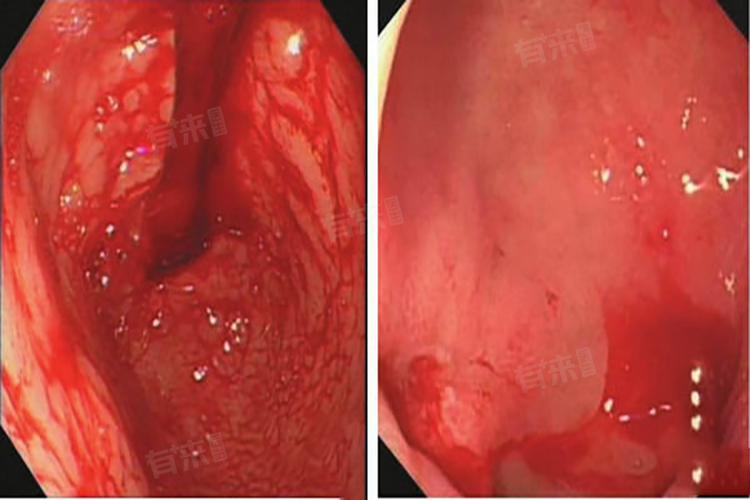

4、胃镜下止血:对于出血严重、症状持续不缓解的患者,应立即就医进行紧急处理,医生可能会根据患者的具体情况,安排胃镜下止血或手术治疗。胃镜下止血是一种有效的治疗方法,可以通过胃镜观察出血部位,并进行止血操作,但对于出血量大、难以控制的患者,可能需要进行手术治疗,以切除病变的胃黏膜或进行血管结扎等。